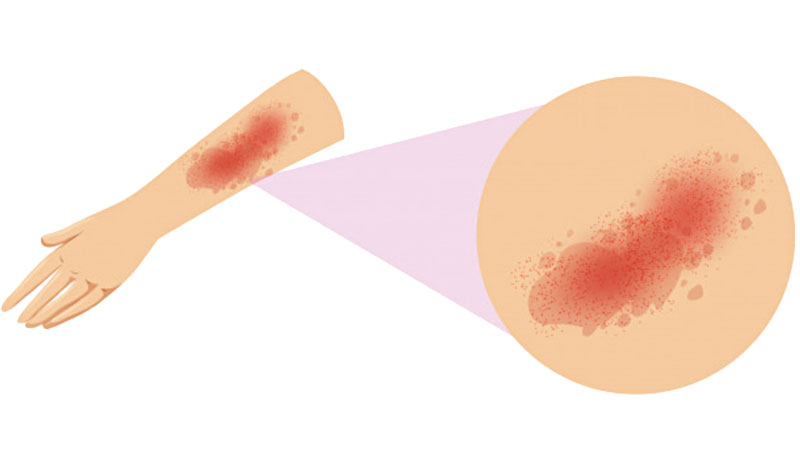

Eczema

About 10 percent of infants and children suffer from atopic dermatitis or eczema. The chronic disease is especially common in families with a history of allergies and asthma. Eczema is extremely itchy, but not contagious, and appears as red, scaly dry skin and can vary in severity.

Physicians generally treat eczema first with an over-the-counter cortisone cream. Throughout the year, treat skin with moisturizers. “Lotions are better in the humid months, ointments in the winter months,” Henry says. “Don’t over-treat if the dermatitis isn’t bothersome.”